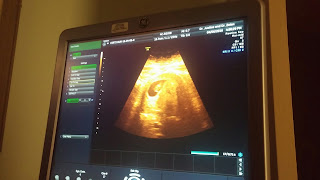

We're pregnant!!!! We did so on our own without the help of doctors or medicines. Our little "Baby Boo" is due November 3 but will likely make his or her arrival a bit earlier (since all our babies like to come a little early). Michael and I along with our children are absolutely excited. We know this baby is nothing short of a miracle and that God is very much in the restoration business. We can not wait to meet our little rainbow baby this fall!

Just a couple quick shots of our little "Baby Boo" at our 10 wk appointment. He or she has a wonderful strong heart beat and is growing on schedule.